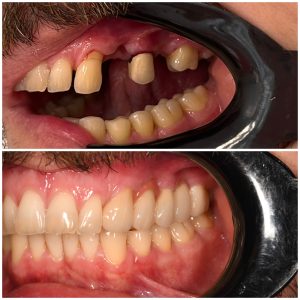

Protetika

Protetika je grana stomatologije koja se bavi rekonstrukcijom i nadoknadom zubnih tkiva usled nedostatka ili gubitka zuba, ili dela zuba

Estetska Stomatologija

Savremena estetska stomatologija koristi materijale vrhunskog kvaliteta koji verno imitiraju prirodan izgled zuba